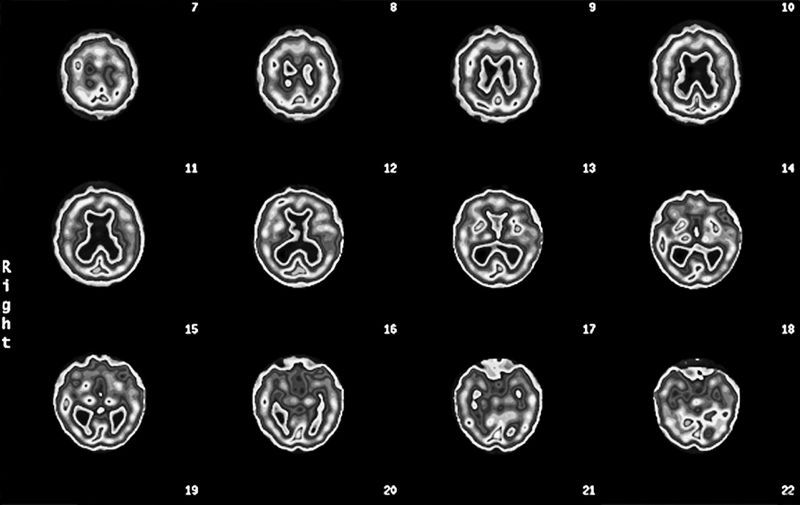

Скан мозга Эда

(горизонтальные срезы мозга показаны по направлению сверху вниз)

См. срезы 15 и 16 и увидите «лобстера»

Скан ОЭКТ мозга Эда

Нетипичная структура для болезни Альцгеймера, мы видим увеличенные желудочки («дыра» в середине) и маленький мозжечок (в основании)

На скане мозга Эда было видно, что желудочки мозга (заполненные жидкостью полости) увеличены. Такой рисунок на томограмме я называю лобстером, потому что он похож на перевернутого омара. Еще у Эда был слишком маленький мозжечок.

Томограмма Эда определенно не походила на типичную картину поражения, которую мы наблюдаем при болезни Альцгеймера (низкая активность височных и теменных долей). Зато картина, как у Эда, часто обнаруживается при заболевании под названием «гидроцефалия с нормальным давлением». При ней блокируется нормальный отток жидкости из желудочков мозга и количество жидкости в них постепенно возрастает.